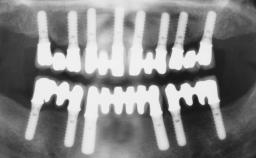

| # of Implants | 8 |

| Bone Augmentation | Horizontal|Staged|Vertical |

| Augmentation Materials | Autogenous block(s) |